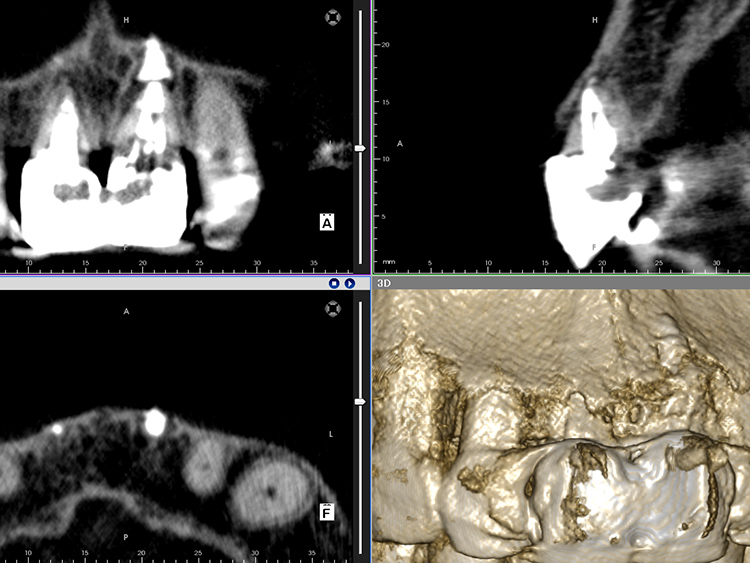

レントゲン検査では、両歯ともに根の先端に大きな病変が認められ、根周囲の骨が広範囲にわたり吸収されていることが確認されました。患者さんご自身の健全な歯質がほとんど残されていない、極めて重症度の高いケースであることがわかります。

レントゲン検査の結果、根の先端にあった病変は治癒し、歯根の周囲に新たな骨の添加が認められます。これは、根管治療で用いた抗菌作用のあるMTAセメントが、カルシウムイオンを持続的に放出することで周囲の硬組織再生を誘導したためと考えられます。